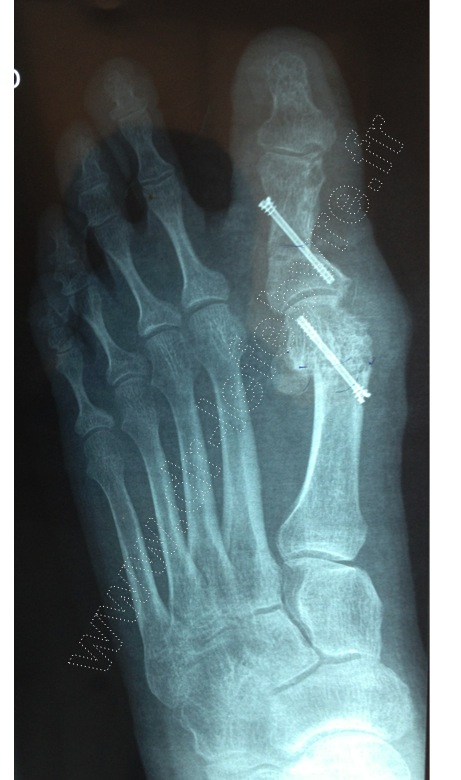

La chirurgie de l’hallux valgus consiste à réaxer le gros orteil par le fait d’ostéotomies du métatarsien et de la phalange. Cette correction d’axe facilite le chaussage en améliorant l’appui plantigrade au sol du pied à la marche et de ce fait les douleurs.

La chirurgie de l’hallux valgus est effectuée par votre chirurgien selon un mode percutané pour limiter l’agression chirurgicale. Elle répond aux mêmes critères de correction que la chirurgie conventionnelle à ciel ouvert tout en bénéficiant des avantages de la chirurgie mini-invasive (moins d’œdème, moins de douleurs, moins de risque infectieux) permettant une récupération fonctionnelle plus rapide.